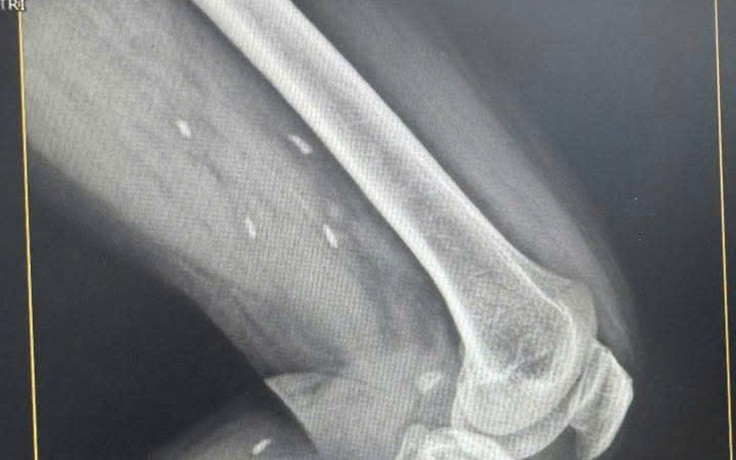

Kén sán rải rác trong vùng đùi và cẳng chân bệnh nhân

Một bệnh nhân tại Quảng Trị sau khi chụp X-quang đã được phát hiện nhiều kén sán rải rác trong vùng đùi và cẳng chân.